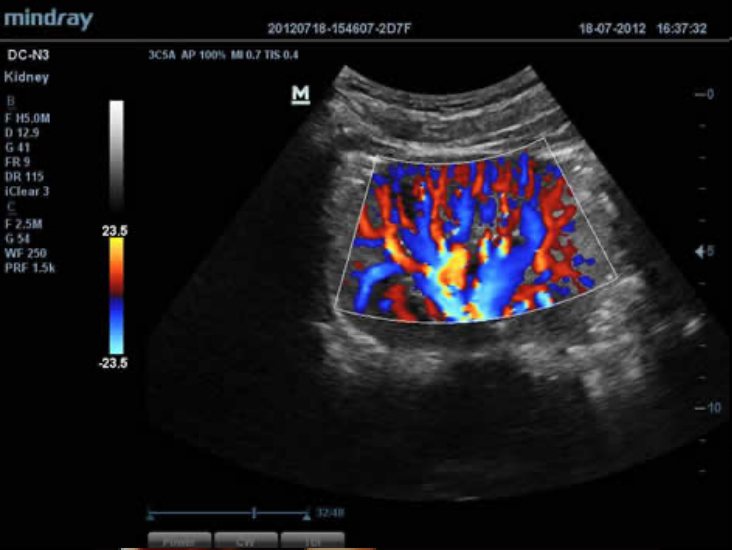

DC-N3 PRO

DC-N3 PRO? ??? ??? ??, ???, ???? ?? ???? ??? ?? ?????. ?? ??? DC-N3 PRO? ??? ??? ?? ??? ??? ???? ???? ??? ????? ??????. ???? ?? ???? ???? ?? ??? ???? ???? ???? ?? ? ????.

DC-N3 PRO? ??? ??? ?? ??? ??? ????? ?? ???? ???? ??? ?? ??? ??? ?? ???? ??? ?????. ?? ??? ??, ???, ??? ?? ??? ??? ??? ?????. ????? ???? ???? ????? ??? ???? ??? ?? ?? ?? ??? ??? ???? ??? ?????.